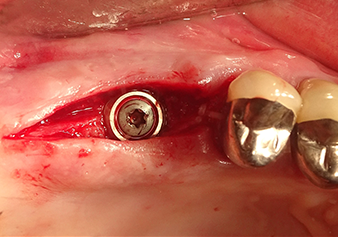

Preoperative findings: The alveolar ridge has healed well, including sufficiently broad, keratinised gingiva

Fig.1: Preoperative findings: The alveolar ridge has healed well, including sufficiently broad, keratinised gingiva.